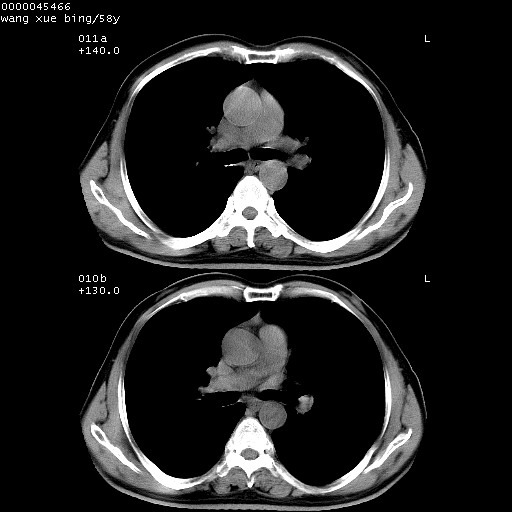

胸部ct轴位平扫(层厚10mm,螺距1.5,重建间隔10mm),图像如下:

右肺下叶团块及不规则空洞,内壁不规则,外缘见粗长毛刺,临近胸膜明显增厚并与病灶关系密切。支持考虑:右肺肺脓肿!建议穿刺病理检查待除外周围型肺癌!

右肺下叶见不规则厚壁空洞,内壁不规则,外缘见粗长毛刺,临近胸膜明显增厚并与病灶关系密切。支持考虑:周围型肺癌!

右肺下叶周围型肺癌伴空洞形成!征象比较明显!分叶、毛刺、胸膜凹陷征、厚壁空洞,壁结节!

空洞壁厚,不规则,其内可见壁结节,周围可见毛刺及阻塞性炎变,多考虑癌性病变.